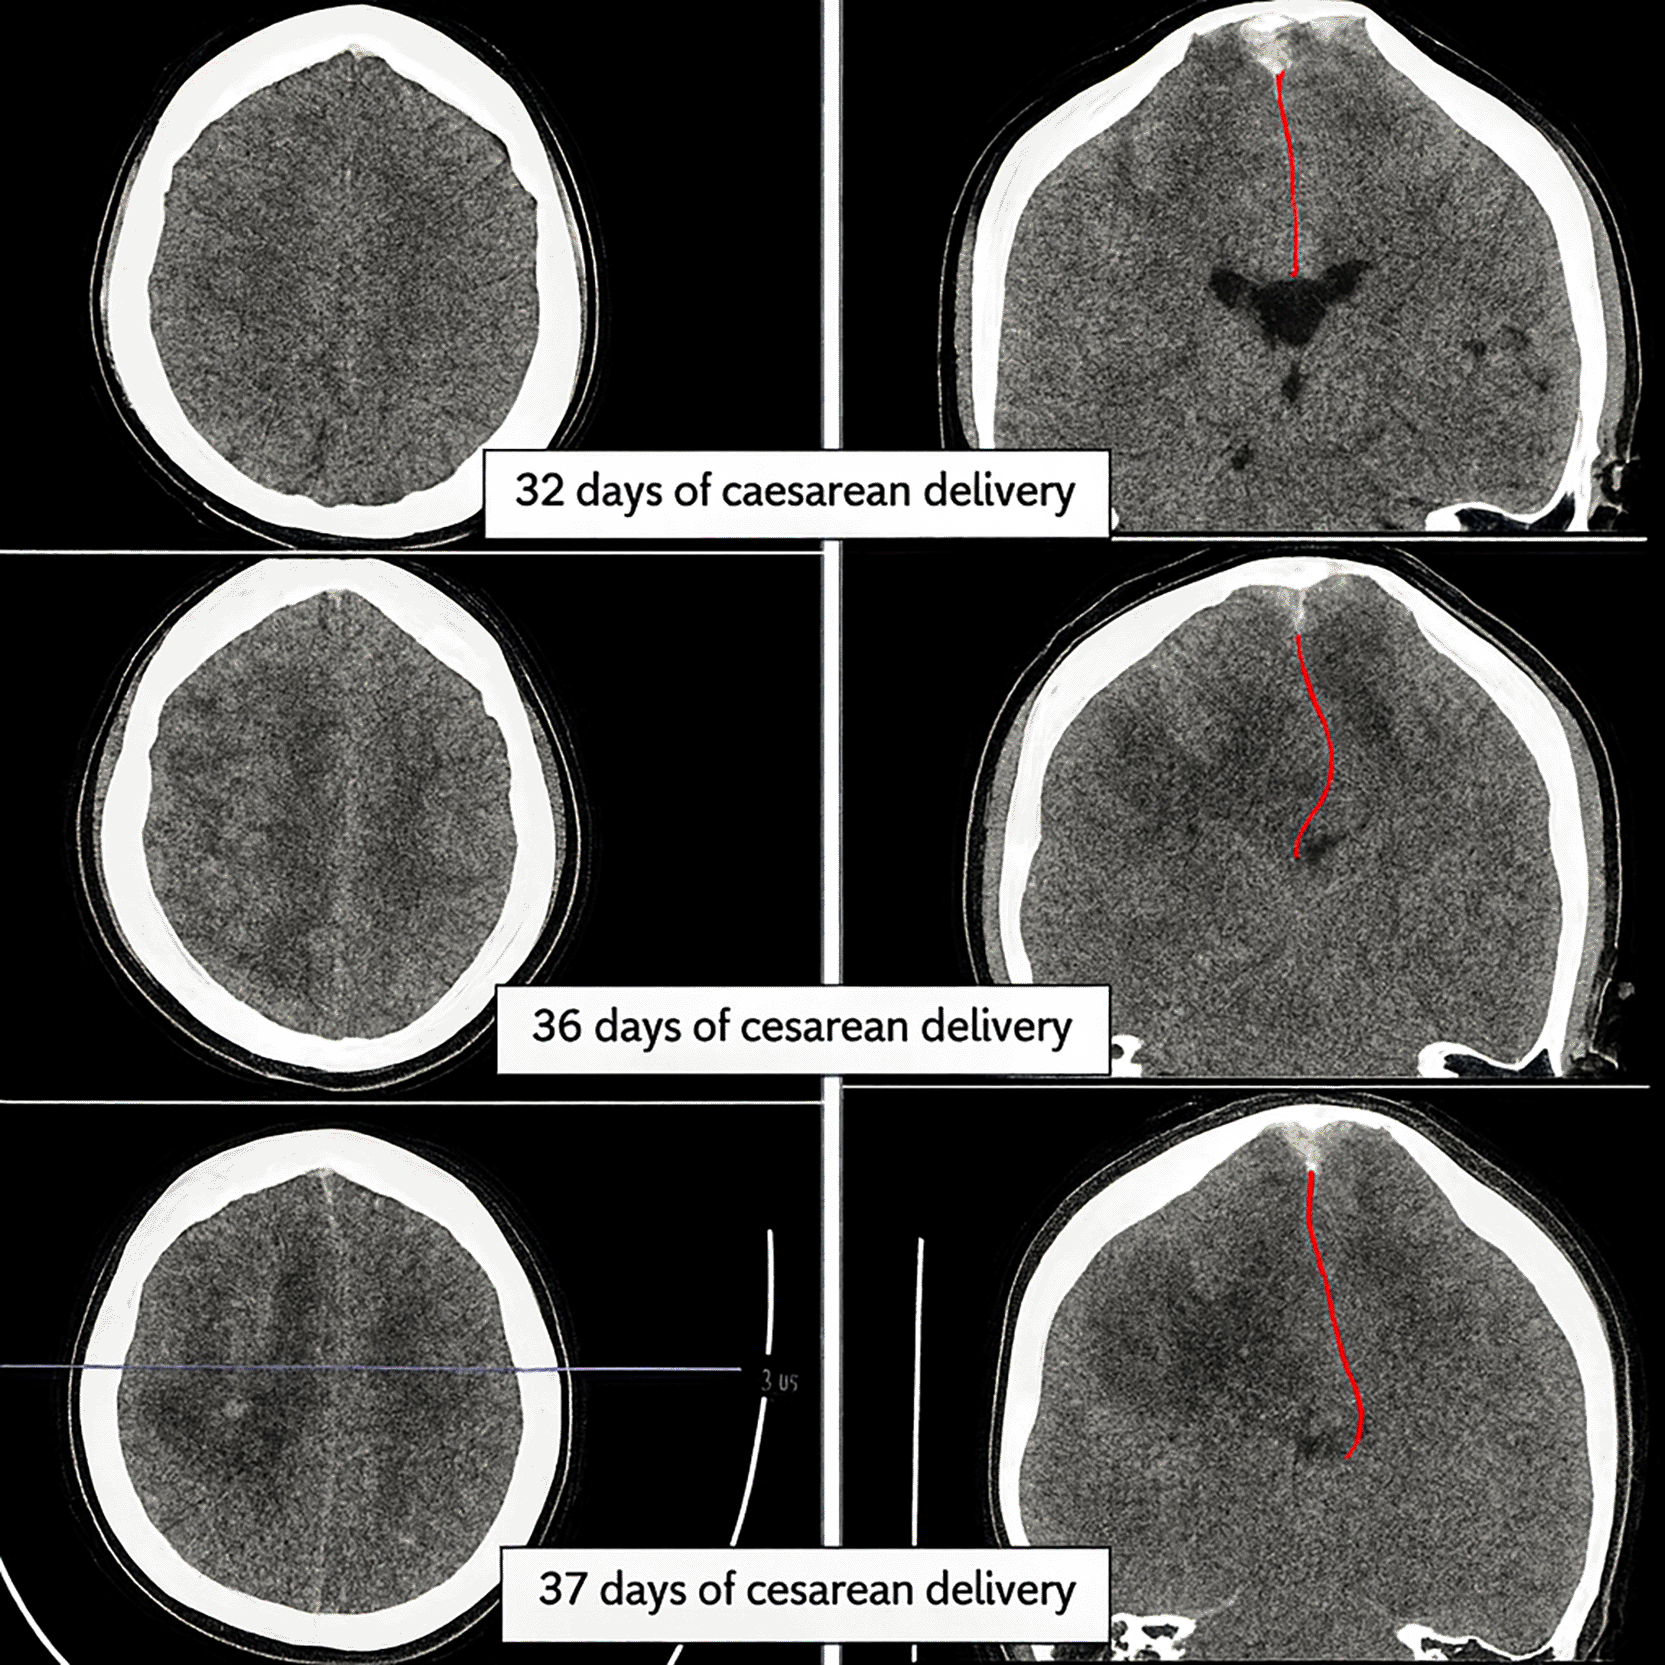

As a result of the tolerable GCS level of consciousness, the neurosurgery division postponed the surgery. Non-invasive hyperosmolar therapy was enhanced by administering mannitol every six hours, incorporating sedation with midazolam at a dosage of 0.1-0.5 mg/kg/hour, and providing Low Molecular Weight Heparin (LMWH) with an initial dose of 5000 IU, followed by 1 mg/kg every twelve hours, along with monitoring PT and APTT to achieve an INR target of 1.5 times the baseline APTT. Due to the absence of coagulability and the presence of persistent fever in the patient’s homeostatic function monitoring during anticoagulant medication, heparinization was terminated. We conducted sequential control CT scans and ultrasound assessments of the Optical Nerve Sheath Diameter (ONSD) to evaluate intracranial pressure (Figures 4-5). We administered third-tier therapy involving intubation, mechanical breathing, and barbiturate treatment, specifically continuous thiopental at a dosage of 1-5 mg/kg/hour ( Figure 6).

At each time point, hemorrhage volume (hyperdense cortical lesion) and mass effect (falcine herniation: red line) were estimated on reference slices to depict lesion progression. Initial examination on day 32 post-cesarean delivery showed venous hemorrhage with less infarction and no falcine herniation (top image). Follow-up examinations on days 36 and 37 showed that the infarction had become more extensive and the falcine herniation had increased relatively significantly (middle and bottom images).